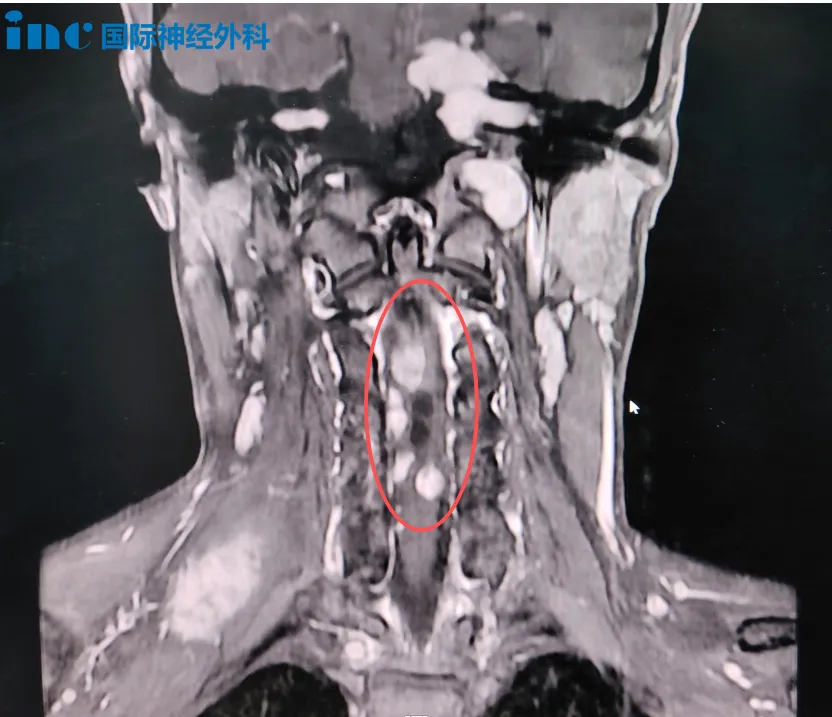

18岁男性患者帆帆的高位颈髓占位病变手术于苏州大学附属第四医院顺利完成。该手术由德国巴特朗菲教授与国内神经外科专家团队共同完成。

患者帆帆的病情特别复杂,病变范围从颈髓内延伸至颈髓外。面对如此复杂的病情,治疗决策变得异常困难。"是否需要手术?手术风险有多大?"家属的担忧既关乎患者当前状况,更关系到其长期预后。经过与巴特朗菲教授的深入沟通,家属了解到颈髓病灶已成为必须面对的关键挑战。

患者确诊为神经纤维瘤病2型,伴有后颅窝、颈髓、腰骶部多发性占位病变,包括听神经瘤、脑膜瘤、室管膜瘤、囊肿等多种类型,需要分次手术处理多处病灶。由于颈髓病灶持续进展可能导致瘫痪风险,首次手术决定优先处理该部位。患者家属最终选择积极面对,坚定接受手术治疗。

手术过程中,巴特朗菲教授首先精确切除了患者髓外多个由系带连接的鞘瘤,消除了首要风险。真正的挑战在于髓内肿瘤,这些肿瘤与正常神经组织交织,边界模糊。凭借精湛的显微手术技术和根深蒂固的神经保护理念,巴特朗菲教授在有限的操作空间内耐心探查,最终在肿瘤与正常组织之间找到分界,实现了满意的切除效果。